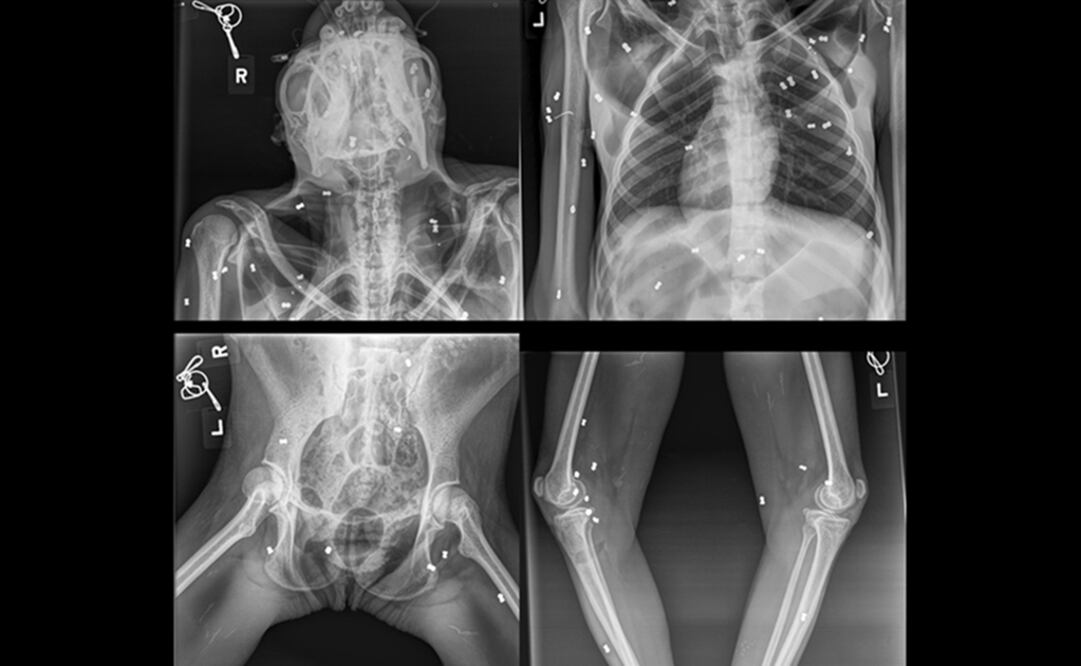

.- Una orangutana fue encontrada con 74 disparos de perdigón en el cuerpo junto a su cría, que murió horas después por desnutrición, en la provincia indonesia de Aceh , anunció este miércoles el Ministerio de Medioambiente de Indonesia.

"La madre presentaba heridas en la mano derecha, la pierna derecha y la espalda, mientras que el bebé de un mes de edad presentaba síntomas de malnutrición", dijo el Ministerio de Medioambiente en redes sociales.

Foto: Twitter @KementerianLHK